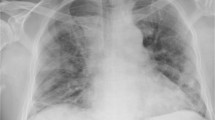

Respiratory complications (RC) are a leading cause of death after spinal cord injury (SCI) due to compromised immune function and respiratory muscle weakness. Thus, individuals with SCI are at high risk of developing COVID-19 related RC. Results of a SCI clinical trial showed a supervised respiratory muscle training (RMT) program decreased risk of developing RC. The feasibility of conducting unsupervised RMT is not well documented. Four publications (nā=ā117) were identified in which unsupervised RMT was performed. Significant improvements in respiratory outcomes were reported in two studies: Maximal Inspiratory and Expiratory Pressure (MIP40% and MEP25%, respectively), Peak Expiratory Flow (PEF9%), seated and supine Forced Vital Capacity (FVC23% and 26%, respectively), and Peak Cough Flow (28%). This review and case report will attempt to show that an inspiratory muscle training (IMT) home exercise program (HEP) is feasible and may prepare the respiratory system for RC associated with COVID-19 in patients with SCI.

A 23-year-old with tetraplegia (P1), history of mechanical ventilation, and hospitalization for RC, completed 27 IMT HEP sessions in one month. MIP and sustained MIP (SMIP) increased from baseline by 28% and 26.5%, respectively. Expiratory volumes and rates also improved (FVC, FEV1, and PEF: 11.7%, 8.3%, and 14.2%, respectively).

The effects of COVID-19 on patients with SCI remains inconclusive, but recent literature and the results of this case suggest that unsupervised IMT is feasible and may limit the severity of RC in patients with SCI who contract COVID-19.